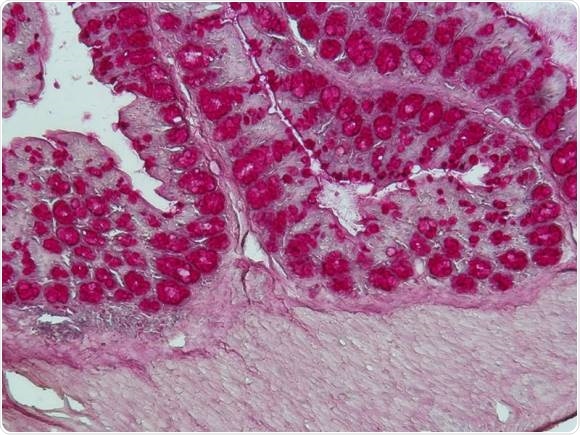

The intestinal microbiota (shown here is a histological staining of a colon section) is significantly influencing the immune system of the host. (Picture: Caspar Ohnmacht / ZAUM)